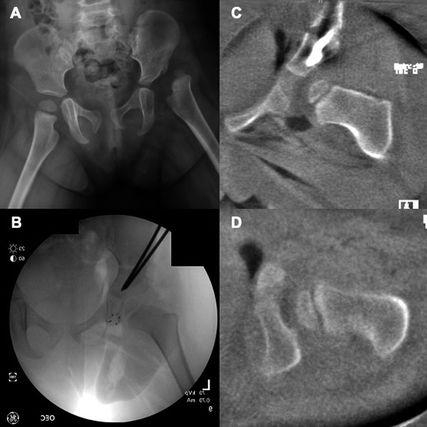

Die Breite des kinderorthopädischen Spektrums, welches man am HSC als Fellow erleben darf, ist einzigartig. Es ist unmöglich, dies kompakt zusammenzufassen, doch ich möchte fast sagen: Es gibt fast nichts, das ich nicht in der Ambulanz gesehen habe oder im OP operieren durfte. Für mich beeindruckend und andererseits auch erschreckend war die Anzahl an unbehandelten kindlichen Hüftdysplasien und Hüftluxationen. Eine Operation, die man in Österreich mit einem universellen Ultraschallscreening bereits fast aus dem OP-Programm verbannt hat, ist die offene Reposition der luxierten kindlichen Hüfte; dies meist kombiniert mit einer Beckenosteotomie (Salter, Dega, Acetabuloplastik, Pemperton) sowie einer varisierienden und derotierenden Osteotomie (VDRO) des proximalen Femurs. In Nordamerika zählt diese Operation noch immer zu den Standardeingriffen der Kinderorthopädie. Ich fühle mich dennoch geehrt, dass ich diesen Eingriff von Simon Kelley, Andrew Howard und Unni Narayanan erlernen durfte, welche wiederum direkt von Rang, Salter und Wedge gelernt haben.

Abb. 3: 2½-jähriges Mädchen mit linksseitiger Hüftluxation. Es wurden eine offene Reposition des Hüftgelenks sowie eine Salter-Beckenosteotomie durchgeführt. A) Beckenübersicht Röntgen präoperativ; B) intraoperatives Röntgenbild; C, D) coronale und axiale intraoperative 3D-Bildwandler-Rekonstruktion